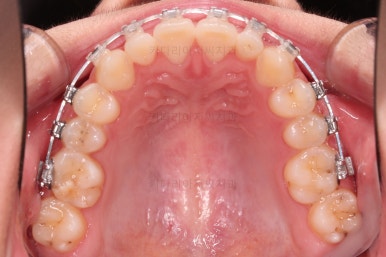

마찬가지로 초진 시 입안의 모습인데요.

위아래 앞니가 삐뚤고, 송곳니는 덧니처럼 불룩 튀어나가 있네요.

위아래 앞니는 안으로 굽어 들어와 있는 옥니(뻐드렁니 반대) 양상이었고요.

그리고 마무리 때 디테일에 문제가 생길 수 있는 부분인데, 윗니 대문니(가장 중간 치아)와 송곳니 사이의 치아를 작은 앞니라고 하는데요.

이 작은 앞니가 가져야 될 크기보다 더 작은 양상이었습니다.

이런 치아를 왜소치라교 표현합니다.

처음 장치를 부착한 모습인데요.

이번 환자분이 부산옥니교정에 사용한 장치는 엠파워 클리어라고 하는 자가결찰 세라믹 장치였습니다.

철사를 잡아주는 캡(결찰)이 브라켓에 달려있어 스스로 묶고 풀고가 가능한(자가) 세라믹 재질의 장치라는 뜻인데요.